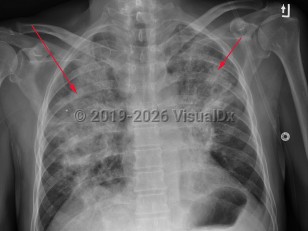

Imaging Studies image of Herpes simplex virus pneumonia - imageId=2953740. Click to open in gallery.  caption: 'Frontal chest x-ray with bilateral air space consolidation, right lobe, (long red arrow), greater than left, (short red arrow).'

Frontal chest x-ray with bilateral air space consolidation, right lobe, (long red arrow), greater than left, (short red arrow).